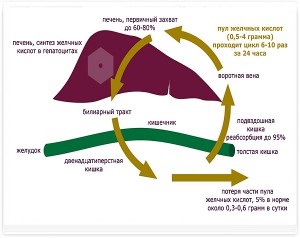

Porto (portocav) șunturi - este conexiuni vasculare anormale între vena portal hepatic (vas de sânge care se conectează tractul gastrointestinal la nivelul ficatului) și circulația sistemică (Figura 2, 2a).

Astfel de anastomoză sanguine anormale directe din tractul gastro-intestinal în circulația sistemică, ocolind ficatul și limitând astfel funcțiile vitale ale ficatului în metabolismul si detoxifiere a produselor metabolice, precum și funcția de barieră de protecție împotriva agenților patogeni intestinali. In astfel de tulburări influențează în mare măsură organismul este supus unor produse toxice de digestie și manifesta simptome de insuficiență hepatică.

Schema Fig.1 a fluxului sanguin normal de portal

Unul dintre principalii indici biochimici este nivelul de acizi biliari. Prin concentrarea acizilor biliari din ser este imposibil de a diferenția boala de ficat, cu toate acestea, în cazul în care concentrația lor după administrarea de furaj este mult crescută (mai mult de 150 mmol / l), putem presupune prezența cirozei sau alt șunt porto.